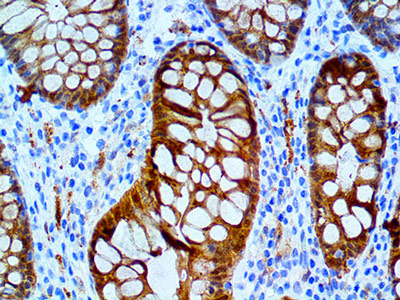

Cadhérine 17

Un nouveau marqueur pour le diagnostic des cancers gastro-intestinaux.

La cadhérine 17 est l’une des cadhérines non-classiques et est également désignée comme LI-cadhérine ou CDH17. Elle est impliquée dans l’invasion tumorale et les métastases...